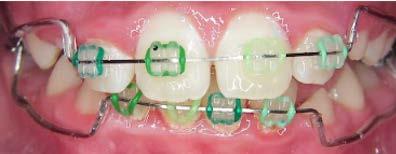

58 | CASO CLÍNICO

Tratamiento de mordida profunda, con arco utilitario, en paciente en crecimiento